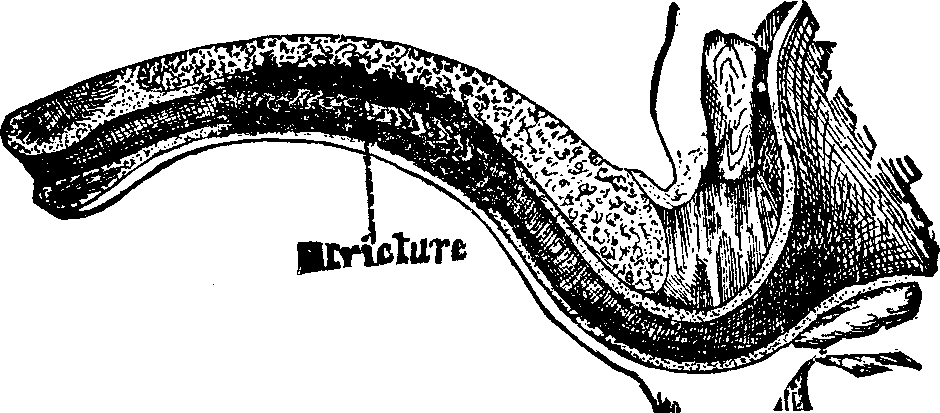

In the obstructive variety of dysmenorrhea, some organic impediment hinders the exit of the menstrual blood from the uterus, which, consequently, becomes distended and painful. The pain may be constant, but is most acute when the uterus makes spasmodic efforts to discharge the menstrual blood. If these efforts prove successful, there is an interval of relief. Flexion or version of the womb may produce partial occlusion of the canal of the neck of the uterus, thus preventing the free flow of the menstrual fluid through it. Tumors located in the body or neck of the uterus often cause obstruction to the free discharge of the menses. Imperforate hymen and vaginal stricture also sometimes cause obstruction and give rise to painful menstruation. As these several abnormal conditions and diseases will be treated of elsewhere in this volume, we omit their further consideration here.

Partial adhesion of the walls of the neck of the womb may result from inflammation of the mucous lining, and prevent a free and easy exit of the menstrual fluid. In many cases, the contracted and narrowed condition of the canal of the cervix seems to be a congenital deformity, for we can trace it to no perceptible cause. It is also true that contraction and partial, or even complete, stricture of the cervix, or neck of the womb, often results from the improper application of strong caustics to this passage by incompetent and ignorant surgeons. Every person has observed the contraction of tissue caused by a severe burn, which often produces such a distortion of the injured part as to disfigure the body for life. A similar result is produced when the neck of the womb is burned with strong caustics. The tissues are destroyed, and, as the parts heal, the deeper-seated tissues firmly contract, forming a hard, unyielding cicatrix, thus constricting the [pg 695]neck of the womb, through which the menses pass into the vagina.

Treatment. From the nature of this malady, it will readily be seen that no medical treatment can effect a radical cure. We must therefore resort to surgery. In a small proportion of cases, the stricture may be cured by repeated dilations of the constricted part of the cervical canal. This may be accomplished by using a very smooth probe which is fine at the point, but increases in size, so that its introduction will widen and expand the orifice and canal. The stricture may be overcome in many cases by using different sized probes. In some instances, we have employed the uterine dilator, represented by Fig. 3. We have also introduced sea-tangle and sponge tents into the neck of the womb, and allowed them to remain until they expanded by absorbing moisture from the surrounding tissues. The latter process is simple, and in many cases preferable. By means of a speculum (see Figs. 15 and 16), the mouth of the womb is brought into view, and the surgeon seizes a small tent with a pair of forceps and gently presses it into the neck of the womb, where it is left to expand and thus dilate the passage. If there seems to be a persistent disposition of the circular fibers of the cervix to contract, and thus close the canal, a surgical operation will be necessary to insure permanent relief. In performing this operation, we use a cutting instrument called the hysterotome (see Figs. 4 and 5). By the use of this instrument, the cervical canal is enlarged by an incision on either side. The operation is but slightly painful, and, in the hands of a competent surgeon, is perfectly safe. We have operated in a very large number of cases and have never known any alarming or dangerous symptoms to result. After the incision, a small roll of cotton, thoroughly saturated with glycerine, is applied to the incised parts, and a larger roll is introduced into the vagina. The second day after the operation, the cotton is removed, the edges of the wound separated by a uterine sound or probe, and a cotton tent introduced into the cervix, and allowed to remain, so that it will expand and thus open the wound to its full extent. This treatment must be thoroughly applied, and repeated every alternate day, until the incised parts are perfectly healed.

Treatment. An extensive observation and experience in the treatment of sterility, convinces us that, in the majority of cases, barrenness is due to some form of disease which can be easily remedied. If the passages through the neck of the uterus be closed or contracted, and this is the most frequent cause of sterility, a very delicate surgical operation, which causes little if any pain or inconvenience to the patient, will remove the impediment to fertility. In many of these cases, we have succeeded in removing the contraction and stricture of the neck of the womb by dilatation. When the vaginal walls are so firmly united as to prevent copulation, a surgical operation may be necessary to overcome their adhesion. When the hymen obstructs the vaginal orifice, a similar operation may be necessary to divide it. Vaginismus, which will be treated elsewhere, sometimes causes sterility.